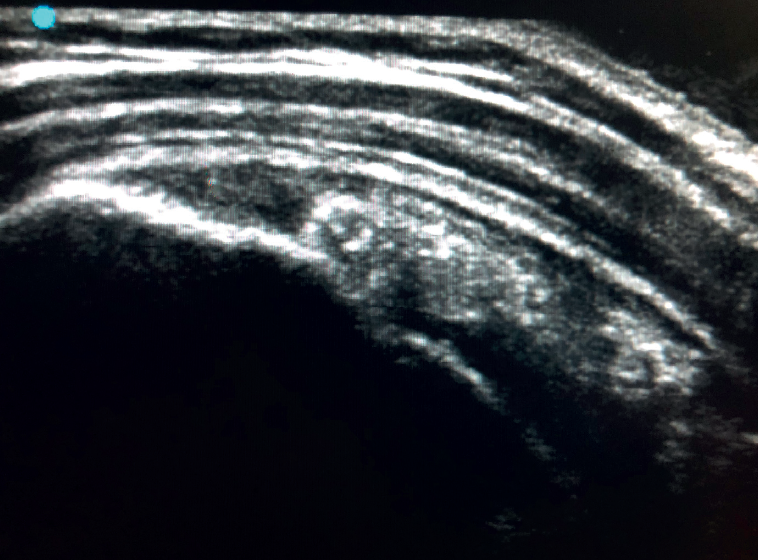

Figure 3. Ultrasound view of severe supraspinatus tendinopathy, with associated bursitis.

The characteristic ultrasound image of tendinosis consists of local or diffuse thickening accompanied by a hypoechogenic and heterogeneous appearance of the tendon (Figure 3). A fine hypoechoic line over 2 mm in thickness between the tendon of the supraspinatus and the subdeltoid adipose tissue corresponds to subacromial-subdeltoid bursitis, and the presence of fluid in the bursa is related to a high probability of partial or complete injury of the tendon of the supraspinatus muscle(26). In order to achieve greater diagnostic accuracy and distinguish between an inflammatory process and a normal small amount of fluid in the bursa, we should take into account that bursitis, tenosynovitis and tendinitis are characterized by the presence of hyperechoic zones with areas of enhanced flow in the Doppler ultrasound study. Both bursal and articular partial ruptures appear as a hypoechoic discontinuity in the tendon that does not vary on modifying the inclination of the ultrasound probe in either the long axis of the tendon nor its short axis(19). This latter aspect is important in order not to confuse partial lesions with anisotropic phenomena, which are a change in tissue behaviour according to the ultrasound angle of incidence(27)(Figure 4).